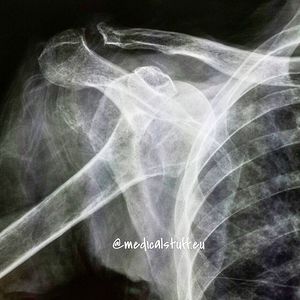

A dislocated shoulder usually happens after a heavy fall onto the arm. It takes between 12 and 16 weeks to heal after the shoulder has been put back into place.Dislocating your shoulder means the ball joint of your upper arm has popped out of the shoulder socket. The surrounding tissues may also have become overstretched or torn.The shoulder is one of the easiest joints to dislocate because the ball joint sits in a very shallow socket. This makes the arm extremely mobile and able to move in many directions, but also means it's not very stable.Most people dislocate their shoulder during a contact sport such as rugby, or in a sports-related accident. In older people the cause is often falling onto outstretched hands, for example after slipping on ice. How do I know if I've dislocated my shoulder?In most cases of dislocated shoulder, the ball part of the joint pops out in front of the shoulder socket. This is usually obvious because:●you won't be able to move the arm and it will be extremely painful ●the shoulder will suddenly look square rather than round ●you may be able to see a lump or bulge (the top of the arm bone) under the skin in front of your shoulderIt's much more unusual for the bone to pop out of the back of the shoulder joint. This usually happens after an epileptic fit or electrocution injury and is less easy to spot.Don't try to pop your arm back in yourself, as this could damage the tissues, nerves and blood vessels around the shoulder joint.